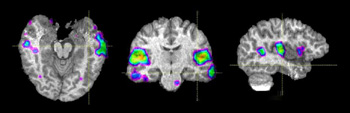

Representación de superficie

La representación de superficie es un método de postprocesamiento en computadora que retira la piel y el cráneo, y nos permite ver la superficie del cerebro. Se muestra la anatomía de las circunvoluciones y los surcos de la misma manera que el neurocirujano ve el cerebro. Pueden superponerse mapas funcionales sobre estas imágenes. Es posible que se produzca cierta activación en la parte profunda de los surcos, la cual puede presentarse en estas imágenes filtrándose a través de la superficie cortical.

Hemisferio derecho en una representación de superficie tridimensional

Joven diestro de 15 años de edad con epilepsia intratable que realiza una tarea de "repetición verbal". La representación de superficie muestra magníficamente la activación que ocurre en el tercio posterior de la circunvolución temporal superior derecha que se extiende hacia la circunvolución supramarginal y el área 7 de Brodmann. Las áreas de activación se muestran mejor que con las imágenes de resonancia magnética bidimensional convencional.

|

Vista angular izquierda posterior superior |

Niña diestra de 11 años de edad con epilepsia intratable sometida a resección frontal izquierda dos años atrás para control de las convulsiones. La persistencia de las convulsiones dio lugar a este examen de IRMf para una nueva evaluación. Las imágenes demostraron una activación obtenida a partir de una "tarea de generación de verbos". El estudio mostró el área de Broca y parte del área de Wernicke (área 37 de Brodmann), las cuales se cree que funcionan como depósito de palabras. Se realizó una segunda resección en función de estos hallazgos. La paciente no experimentó afasia postoperatoria y hasta la fecha no ha vuelto a tener convulsiones.